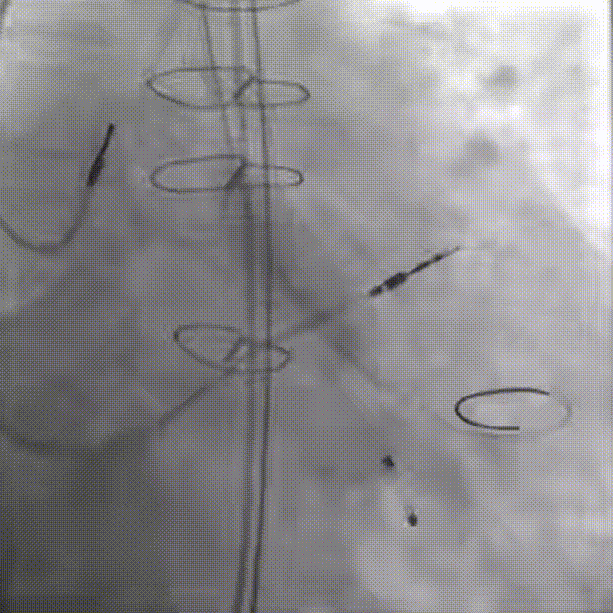

22mm球囊后扩(1.0倍速播放)